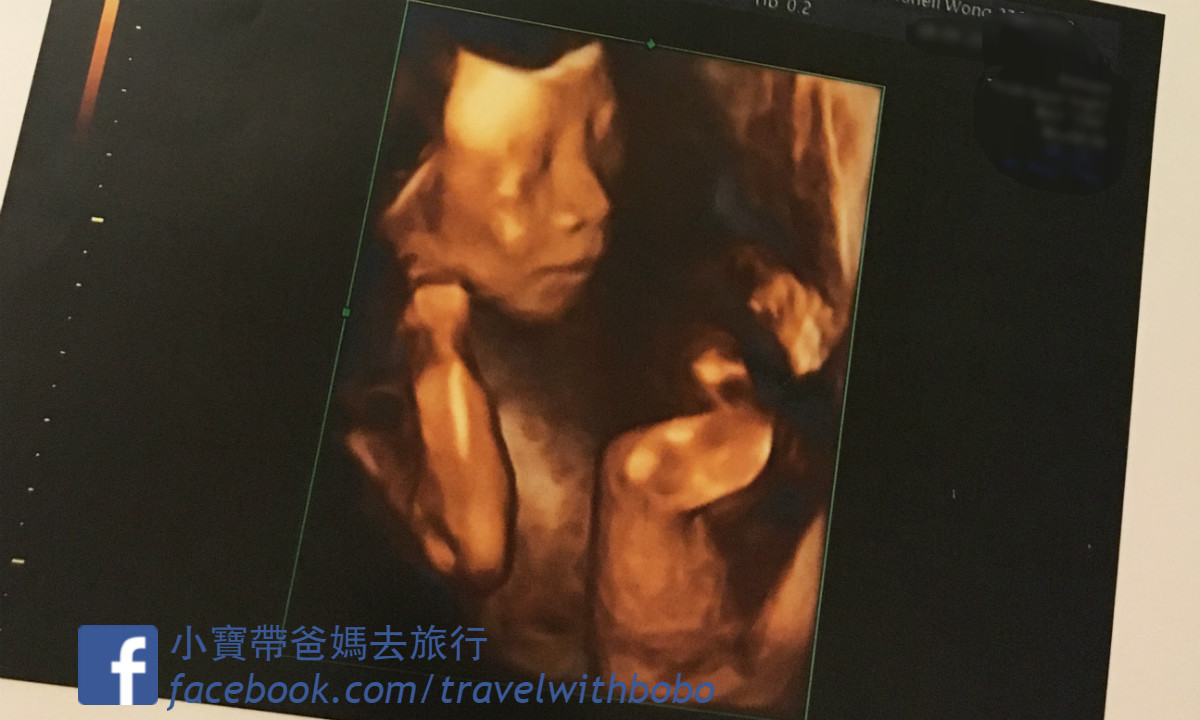

結構 超聲波

» 結構 性 超聲波 2d 3d 4d 分別 (99) 사진

結構 性 超聲波 2d 3d 4d 分別 (99) 사진